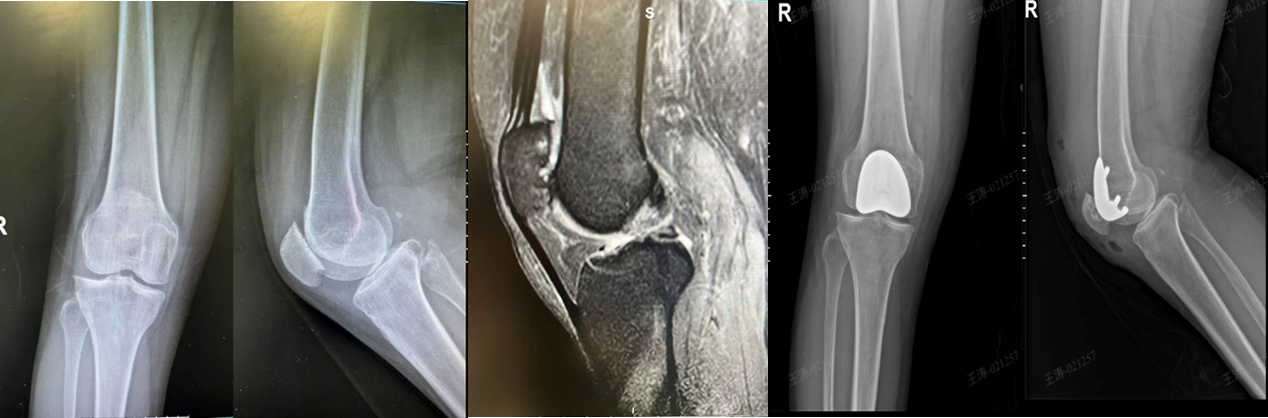

单髁膝关节置换术如同精准置换“损坏的房间”,适用于仅单一间室(多为内侧)严重磨损,但前后交叉韧带、其他间室及髌股关节均功能良好的患者。技术精髓在于仅置换膝关节受损的“一半”,创伤更小、出血更少。核心优势体现在快速康复与极致仿生,术后第二天即可下地行走,康复速度明显快于全膝置换。更重要的是,它最大限度地保留了膝关节自然的生物力学和本体感觉,患者术后常感觉“几乎忘了膝盖做过手术”,尤其能满足散步、旅游、甚至适度运动的需求。

单髁膝关节置换术(UKA)

髌股关节置换术则专注解决“膝前痛”,常见于上下楼、下蹲时疼痛加剧,而其他间室完好的患者。技术精髓在于仅对髌骨和股骨滑车表面进行置换,保留了膝关节内外侧的健康结构及所有韧带。核心优势在于针对性根除特定痛苦,术后患者上下楼梯、起身下蹲的疼痛得到明显缓解,同时避免了为局部问题而置换整个关节的“过度治疗”。这是解决孤立性髌股关节炎的终极微创方案,能有效恢复膝关节伸屈功能,缓解特定疼痛。

髌股关节置换术(PFA)

UKA+PFA(单髁膝关节置换术+髌股关节置换术)联合手术是双间室病变的“微创组合修复方案”,适用于同时存在内侧间室与髌股关节严重磨损,但外侧间室及膝关节关键韧带(如前交叉韧带)功能完好的患者。通过一次手术、一个切口,精准置换内侧间室和髌股关节,完整保留健康的外侧间室以及膝关节所有的原生韧带与运动机制。相较于传统的全膝关节置换,它实现了“2/3个膝关节的微创置换”,保留了患者自身关节超过三分之一的原生结构。核心优势在于最大程度上避免全膝置换,既能同时解决行走负重痛和膝前活动痛,又保有了部分天然关节的感觉与功能,具有创伤小、出血少、康复快、本体感觉保留佳的优势。

单髁膝关节置换术+髌股关节置换术(UKA+PFA)